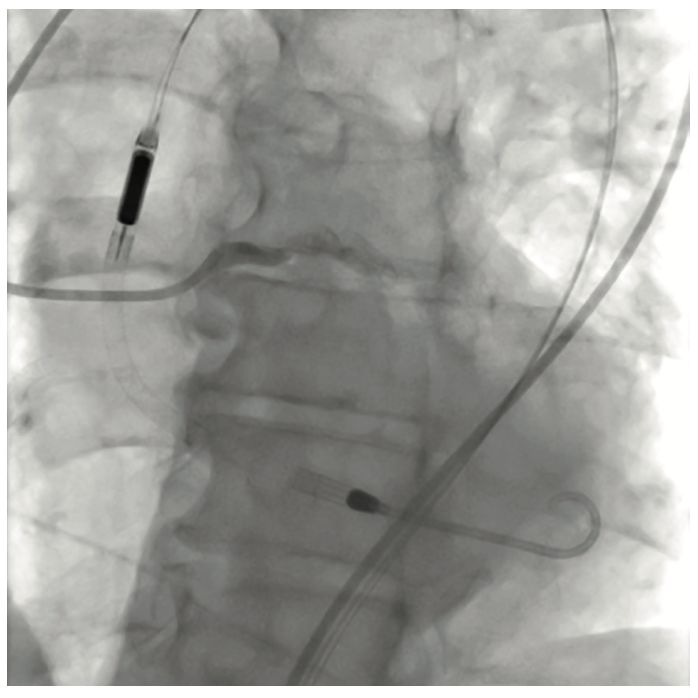

The initial interventional attempt via a transradial approach was unsuccessful due to significant vessel tortuosity. Therefore, a high risk protected PCI was attempted via left femoral access using an Impella 2.5L device (Abiomed) for left ventricular support. The Impella 2.5L was placed via the right femoral access. Before the engagement of coronary arteries, the patient had deteriorated clinically with hypotension and Impella support dropping to 1.4L. Subsequently, the patient went into VT/VF arrest, requiring cardiopulmonary resuscitation (CPR). The patient was emergently intubated. During active CPR and VT storm, selective injections of the left main coronary artery were performed, revealing total thrombotic occlusion of distal left main artery. The patient underwent multiple percutaneous transluminal coronary angioplasties of the left main, ostial and mid LAD, and LCx (OM1) lesions. This was then followed up with stenting of the mid left main into the ostial LAD and LCx (OM1) branch. The coronary interventions were performed during CPR. The patient received a total of 13 defibrillator shocks, and was given intravenous amiodarone and lidocaine pushes during CPR. Return of spontaneous circulation was obtained after 45 minutes. Due to extensive PAD, the Impella device was removed and an intra-aortic balloon pump was placed via a left femoral approach for continued hemodynamic support.